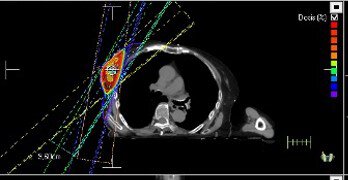

SABR treatment planning